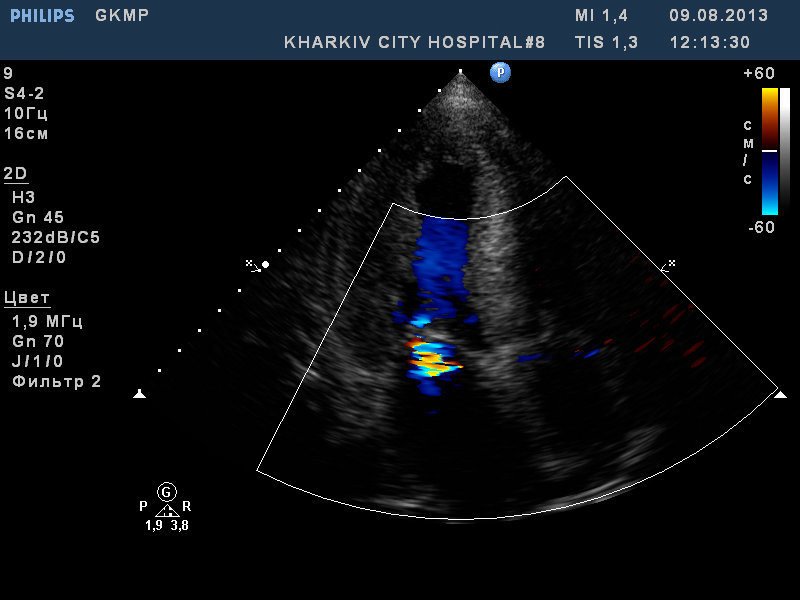

ГКМП

ГКМП. обструкции кровотока в выносящем тракте левого желудочка нет.